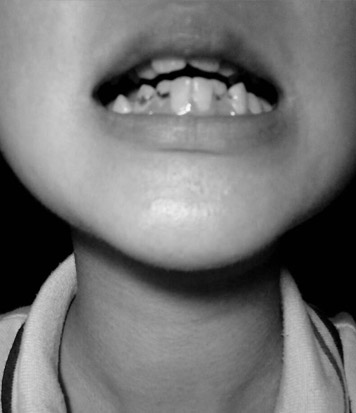

美莱Invisalign隐适美医生会进行拍照、X 光检查和数字扫描或取模,以便为您制定治疗方案。

医生进行检查

制定治疗方案